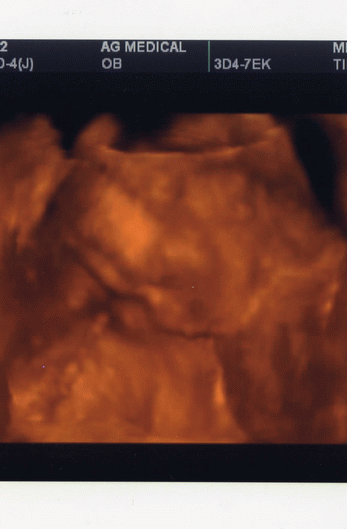

1000% hogy kisfiú, és mekkora van neki :lol: jó nagy :lol: Elkezdett szépen növögetni, már egy héttel nagyobb a koránál :D becsült súlya 365 gramm. Ha valakit érdekel: bpd 50 mm, ofd 63 mm, hc 180 mm, ac 163 mm, fl 30 mm, efw 365 mm. A lábacskája rövidebb a koránál egy héttel, lehet törpi lesz :lol:

Folyamatosan ficergett, játszott a köldökzsinórral, össze-vissza tekergette magán :shock: :lol:

Kép Öcsike feje oldalról, a fejére rálóg a köldökzsinór :)